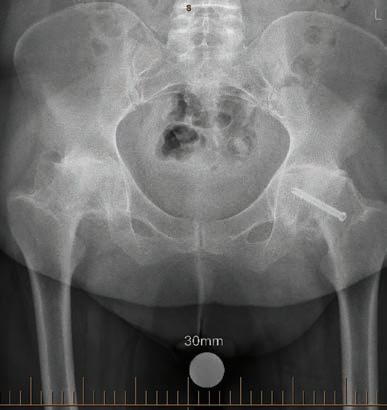

WINPREMIUM WINESFROMWEST C A P E EWOH 16 CONNECT WITH US /medicalforumwa /MedicalForum_ /medical-forum-wa-magazine info@mforum.com.au www.mforum.com.au

5 Bulk-billed genetic carrier screening Dr Minette Saad 40 Mammographic breast density Dr Eric Khong 42 Menopause & women’s health, wellbeing & productivity Dr Purity Carr & Dr Christabel Samy Guest Columns 10 Call for more inclusive primary care Dr Roanna Lobo 31 Concussion guidelines support safe decisions Dr Sarah Hellewell 45 Hormonal management in endometriosis Dr Jennifer Pontré & Dr Bernadette McElhinney 51 Diet therapies & IBS Ele Stojanoska 52 Robotic-assisted hip & knee replacement outcomes Dr Dan Marshall 55 Uterine fibroid embolisation Dr William Ormiston 46 Ovarian endometriomas Dr Sean Copson 49 Ovarian reserve Dr Santanu Baruah 37 Age-old problems set to haunt Mark Woodland